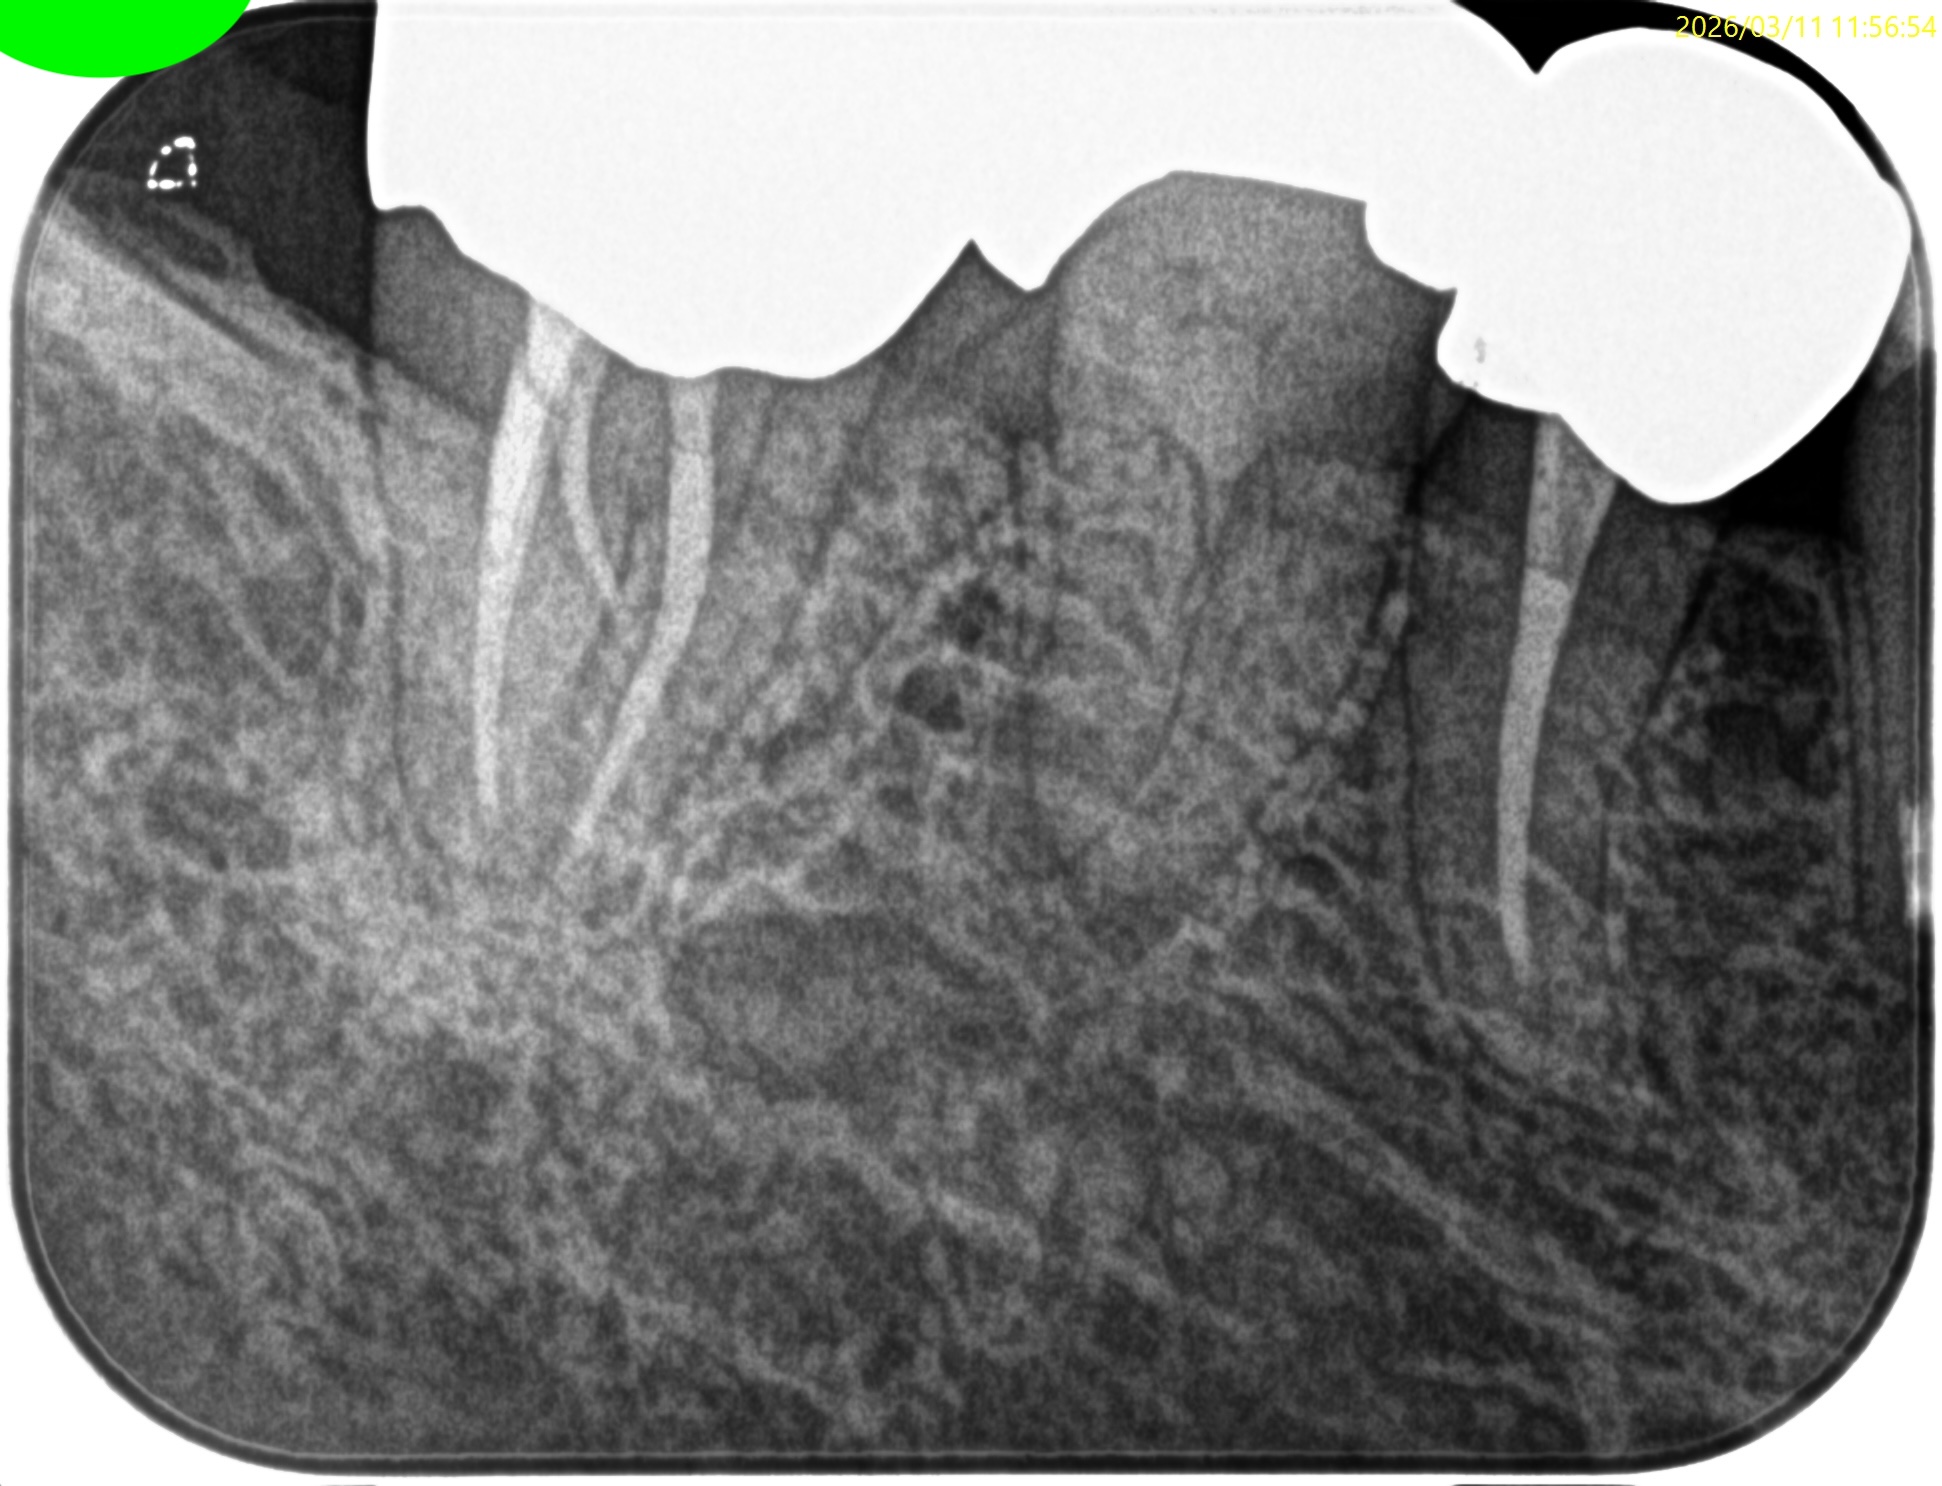

術後にPA, CBCTを撮影した。

MB

ML

D

Radix

ということで問題ないだろう。